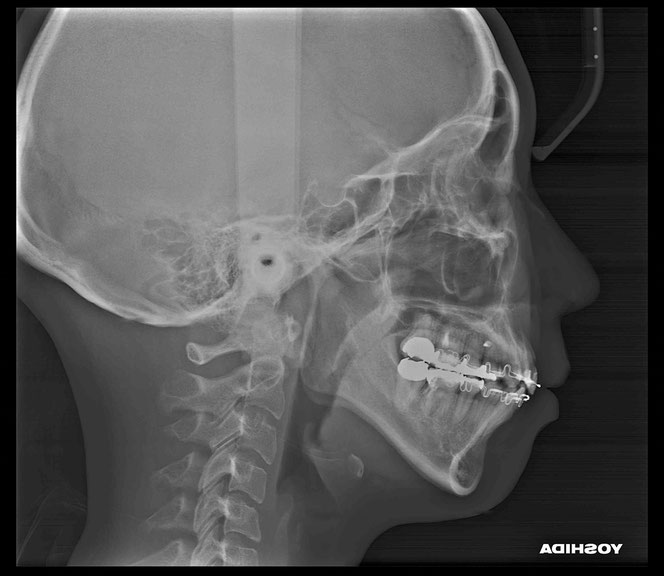

今回のケース

矯正治療後に奥歯の歯ぐきが2~3ミリ退縮。

その結果、露出した根の一部が虫歯になっていました。